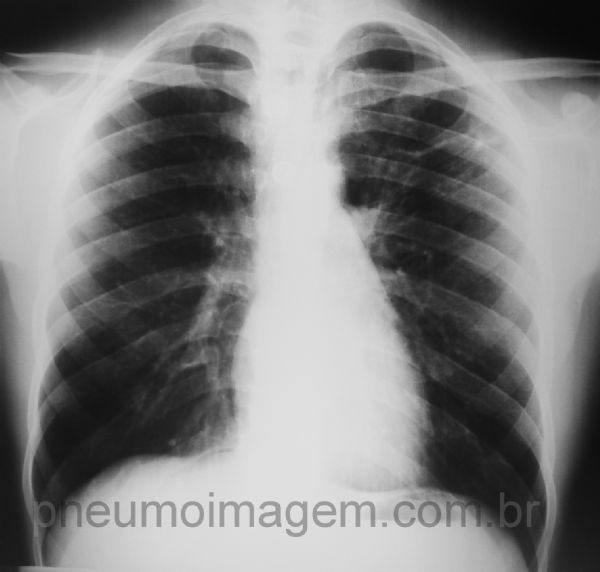

Tuberculose em lobo superior esquerdo

Opacidades alveolares e intersticiais no ápice esquerdo em caso de tuberculose pulmonar.

Alveolar and interstitial opacities in the left apex in case of pulmonary tuberculosis.